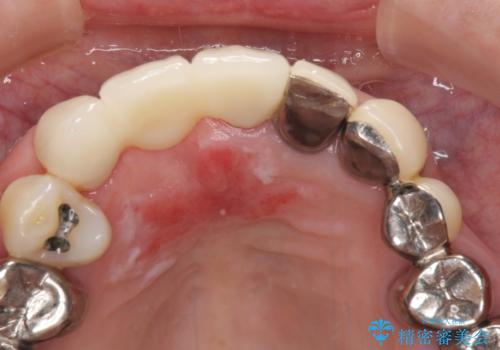

仮歯に置き換えた時点で見た目が大きく改善され、人目を気にすることがなくなりました。

オールセラミッククラウンは、仮歯以上に快適な舌触りや、本物の歯のような外観となり、患者様には大変満足していただけました。